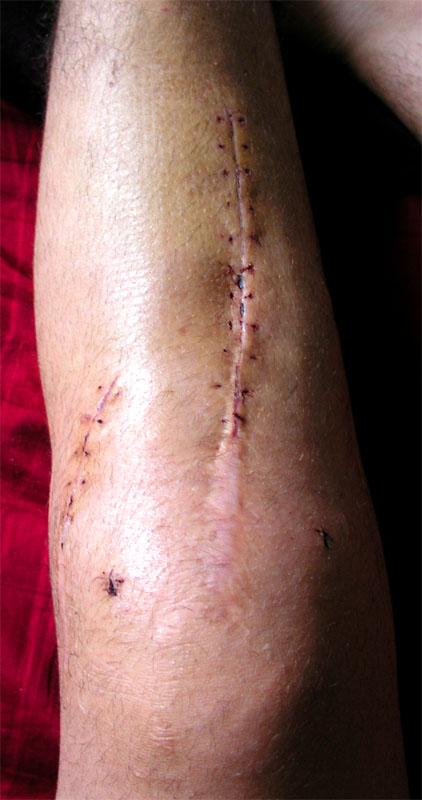

9. August 2005, 20.45 Uhr: Blutrote Alpen

Dr. Kotsaris, Oberarzt von Prof. Stäubli, muss seinen Ausgang leider kurz unterbrechen; die untere Narbe blutet stark nach. Momentan reiche aber hochlagern. Abendrot - aufs Bild klicken für grössere FassungIm Gespräch deutet er nochmals an, dass meine Gelenksflächen sehr stark geschädigt seien; dass die ausgeführte Operation aber das einzig Richtige momentan sei. Eventuell müsse man vor dem künstlichen Gelenk noch ein, zwei Mal Arthroskopien vornehmen, in denen versucht werde, den Knorpel weiter zu erhalten. - Claudia, Agnes und Eliane machen Stippvisite - fast schon wie daheim... Blutrot verfärben sich auch die Berner Alpen; das Abendrot über Eiger, Mönch und Jungfrau versüsst den dritten Ausflug ans Fenster (aufs Bild klicken für grössere Fassung).

Samstag, 20. August 2005: Schwarzes Blut

Oh, bitte nicht... inzwischen wurde ich netterweise von nahen Verwandten in die Berge verlegt und werde wunderbar betreut, und auch wenns hier in Wengen in Strömen schifft, würde ich doch meine Zeit gerne anders als beim Dorfarzt verbringen: Durch eine kleine Lücke in der Narbe hat sich nachts der eine Bluterguss am Schienbein in den Verband entleert, ekliges dunkles dickflüssiges Blut... sollte nun aber wieder OK sein. Ist ja vor vier Jahren am Beckenkamm auch schon mal passiert. Trotzdem, kein angenehmes Gefühl, vor allem wenn man keine Ahnung hat, was die Schmerzen bedeuten: Infekt? Normaler Heilungsprozess? Überbelastung? Wer sich das partout anschauen will...

Montag, 22. August 2005: Wasser, Wasser, Wasser

Thema des Tages ist das Hochwasser - da ist mein Knie nebensächlich. Wenige Meter von meiner Hochwasser 22.8.2005 - Klicken für grössere FassungWohnung entfernt spielt sich eine Tragödie ab. Die Aare fliesst mitten durchs Quartier, das Wasser hat eine unbändige Kraft. Was für ein Kontrast zum friedlichen Fluss noch vor wenigen Tagen. - Nun, im Salem war zum Glück nichts überschwemmt. Die Fäden wurden nur teilweise gezogen, da die Narbe in der letzten Nacht wieder aufgegangen ist und dunkles Blut sich den Weg nach aussen gesucht hat. (Aufs Bild klicken für grössere Fassung)

Freitag, 26. August: Alle Fäden draussen

Klicken für grössere FassungHeute wurden alle Fäden gezogen, die dritte Physio lief gut - langsam habe ichs gut im Griff, wieviel ich forcieren darf, ohne nachher allzu starke Schmerzen Klicken für grössere Fassungzu haben. Allzu lange halte ichs nicht aus, ohne das Bein hochzulagern; der Bluterguss ist aber schön zurückgegangen und das ganze sieht recht gut aus. Der Befehl lautet: Hochlagern, so viel üben wie schmerzfrei geht, das Gelenk in Bewegung halten. - Fast vergessen: In meiner Akte habe ich ein neues Arthroskopiebild entdeckt.